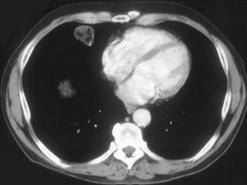

男,57岁,体检时发现肺部占位,CT检查如图,请选出最可能的诊断 ( )A、肺转移瘤B、肺曲菌病C、周围型肺癌D、肺结核E、肺错构瘤

问题 男,57岁,体检时发现肺部占位,CT检查如图,请选出最可能的诊断 ( )

选项 A、肺转移瘤 B、肺曲菌病 C、周围型肺癌 D、肺结核 E、肺错构瘤

答案 E